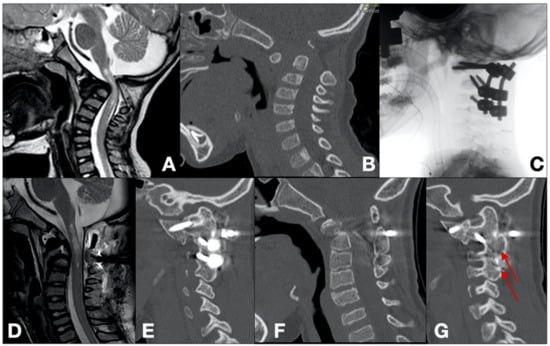

- Case 4 (Figure 3)